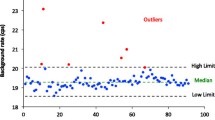

Figure 3 shows the distribution of activity conversion factors calculated using a 99mTc source scanned on the Philips Precedence SPECT/CT gamma camera. The graph displays the results generated from the various phantoms and geometries used: the 20-cm cylindrical phantom with and without 3 cm of TEM material added; the ACR and IQ cylinder phantoms; along with the 1-, 2-, and 4-L bottles.

Graph of the conversion factors for 99mTc complete data set over the entire 18 months of the study. Data set includes all phantoms, 20 cm, ACR, and IQ (solid diamond) and all liter bottles: 1 (circle)-, 2 (triangle)-, and 4 (square)-L. 72.5 % of the data points are within one standard deviation of the mean

As seen in Fig. 3, during the first couple of months of the study, the conversion factors remained just above the mean, and then started to drift below. Calibrations and preventive maintenance (PM) were performed on the scanner on 5 October 2012, after which there was a decrease of approximately 4 % in conversion factors derived from the cylindrical phantom for that month. The conversion factors then began a slight shift upward. Prior to and up to the PM, there was an overall increase in the conversion factors of 4 %. In April of 2013, the center of rotation calibration (COR) and adjustments were made along with a second PM. Following the COR and PM, the conversion factors then remained relatively constant. With a few exceptions, the conversion factors remained below the mean staying within 1.5 %. However, for example, on 17 January 2013, four studies of the same ACR cylindrical phantom were taken at different time periods and all were above the mean. In these instances, the increase in conversion factors may be due to the use of the ACR phantom or may have been influenced by other constituents. Unfortunately, only one set of data was collected with the ACR phantom and on 17 January 2013, the option of obtaining the 20-cm cylinder phantom for a direct comparison was not available.